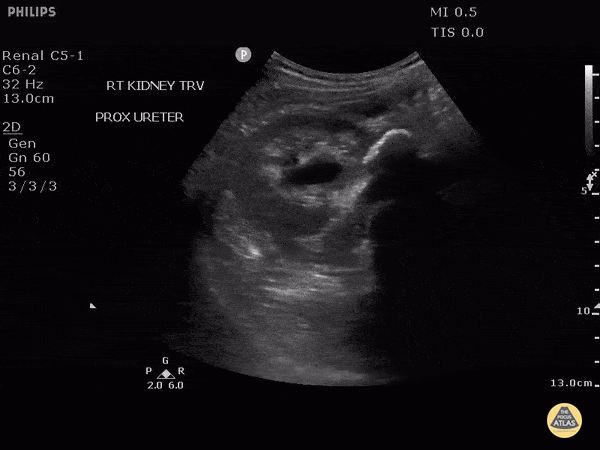

This patient presented with fever and flank pain with a known history of medullary nephrocalcinosis. Here we can see internal echoes within the dilated collecting system consistent with pyonephrosis. A large stone can be seen in the proximal ureter as a hyperechoic line with posterior shadowing. Image courtesy of Robert Jones DO, FACEP @RJonesSonoEM Director, Emergency Ultrasound; MetroHealth Medical Center; Professor, Case Western Reserve Medical School, Cleveland, OH View his original post here